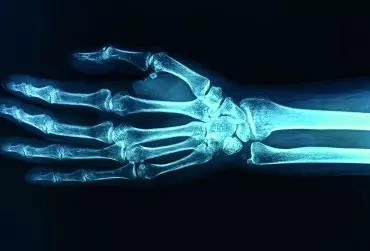

Diagnostyka różnicowa pachwiny i stawu biodrowego – część 2

Bóle okolicy pachwiny i stawu biodrowego mogą mieć różne podłoże – od zmian przeciążeniowych i zwyrodnieniowych, przez usidlenia gałązek nerwowych, aż po bardzo groźne choroby infekcyjne i nowotworowe. Ze względu na to, że różne schorzenia mogą wywoływać podobne objawy, warto zapoznać się z zasadami badania klinicznego i diagnostyki obrazowej tego rejonu.